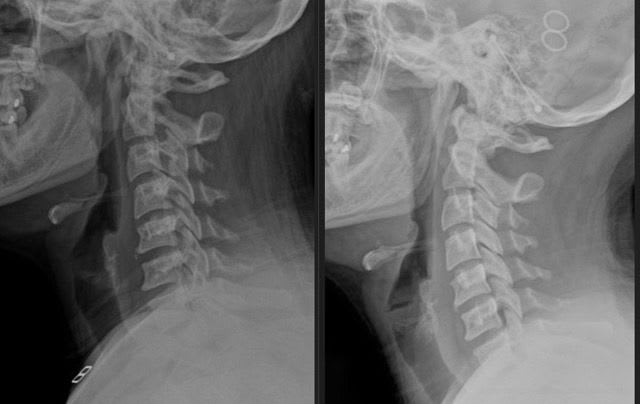

Tech neck, also known as forward head posture, develops when your head shifts out of alignment from constant phone and computer use. Learn how to recognize it and how we correct it at the source.

Even minor car accidents can cause lasting damage to your spine and nervous system, often without immediate pain. Learn why early evaluation is critical and how we correct the damage at its source.

So much of our lives put us in to bad postures and positions that over time can negatively impact our health and quality of life. At 5280 Chiropractic, we use chiropractic and exercise to correct chronic posture patterns.